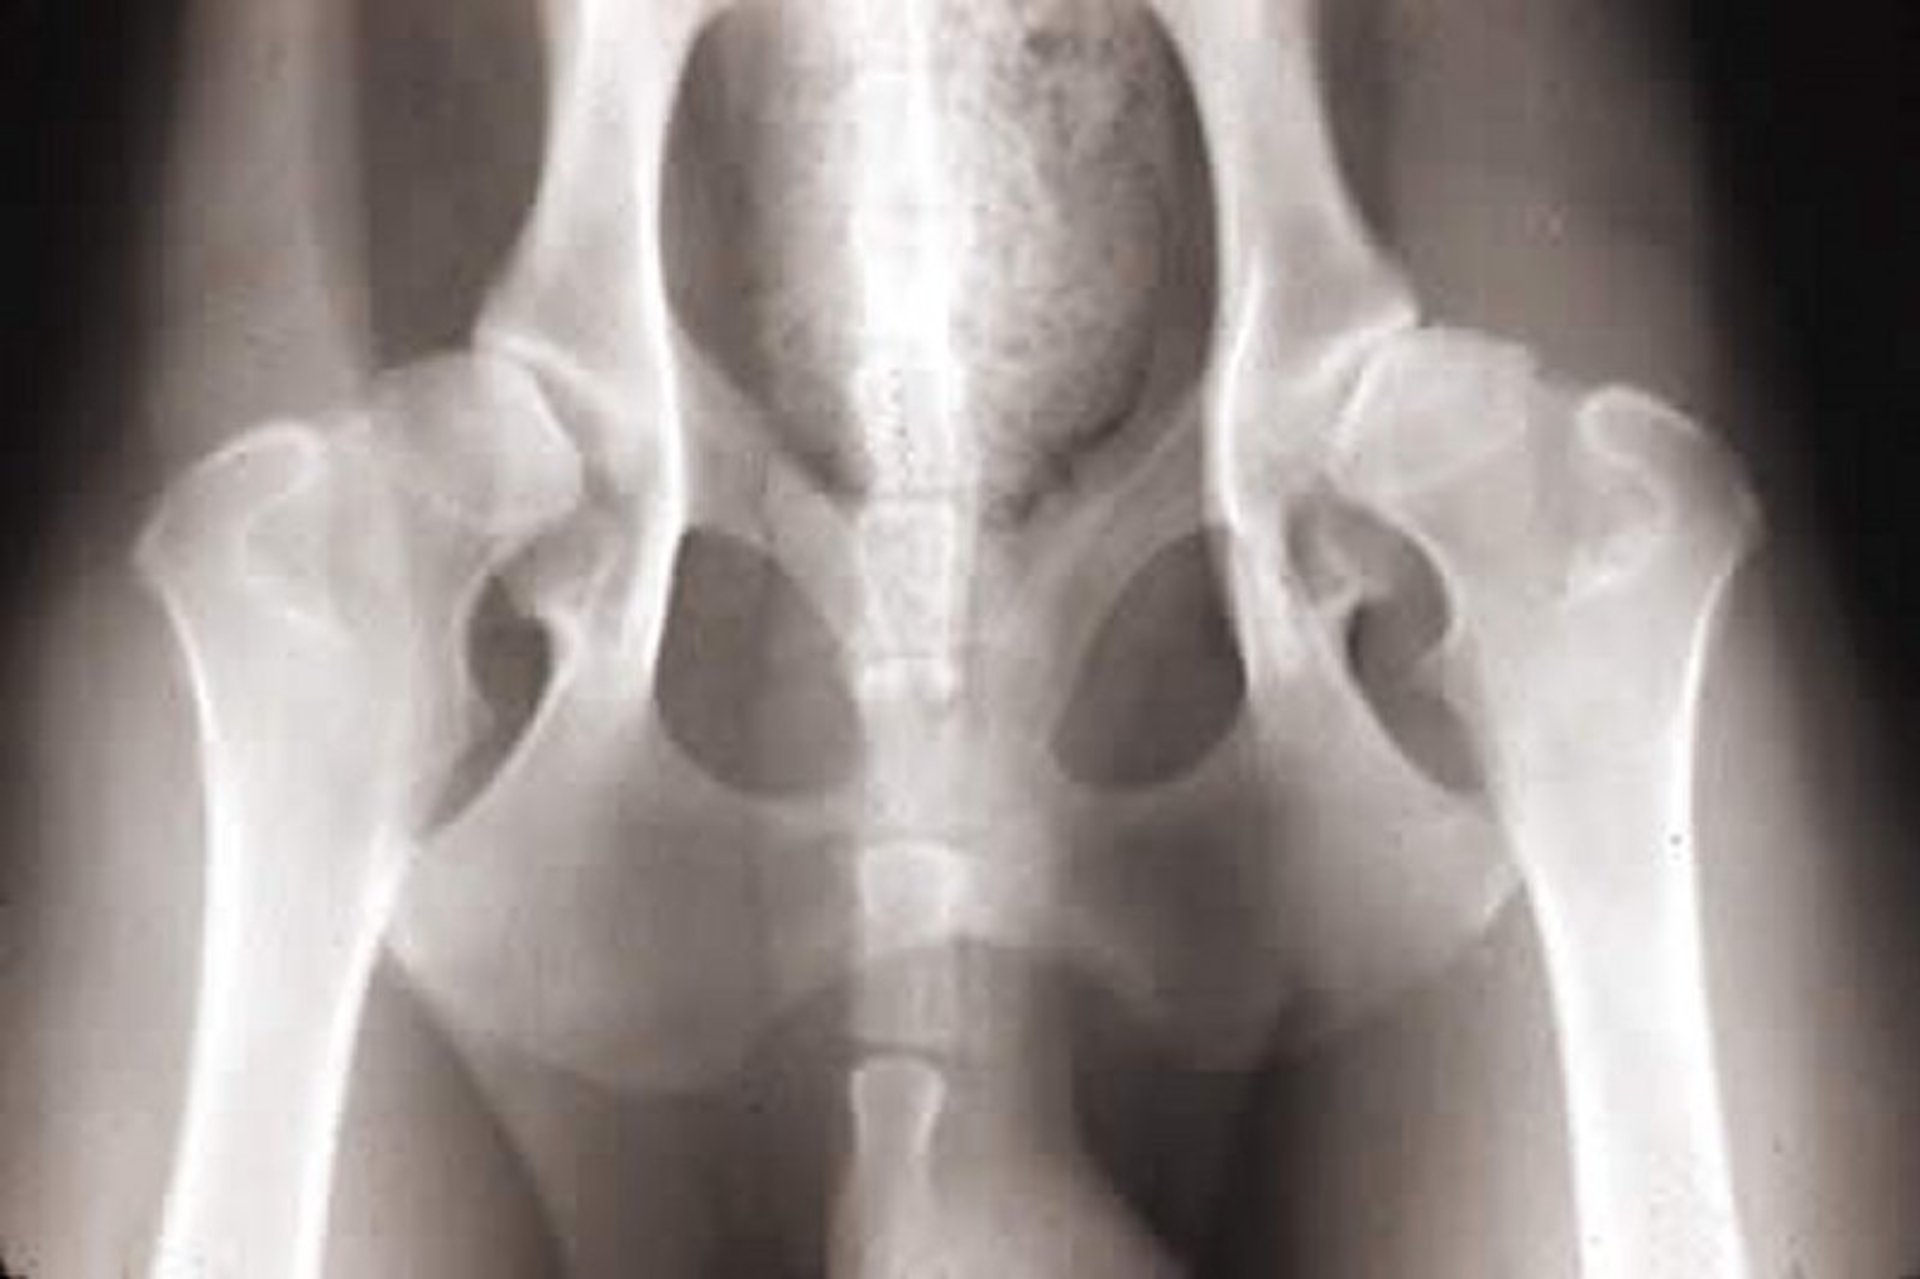

The pathophysiological basis of hip dysplasia is a disparity between hip joint muscle mass and rapid bone development. As a result of this disparity, coxofemoral joint laxity or instability develops and subsequently leads to degenerative joint changes such as acetabular bone sclerosis, osteophytosis, thickened femoral neck, joint capsule fibrosis, and subluxation or luxation of the femoral head (see ).

Courtesy of Dr. Ronald Green.